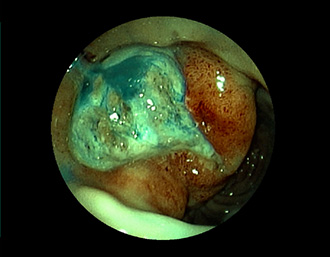

症例2:胃がん(66才男性)

術後胃(B-Ⅱope magen:十二指腸潰瘍手術)。吻合部の後壁側、軽度陥凹の白色病変を認める。生検:Group 5、Signent-ring cell carcinoma(印環細胞癌)と診断[早期胃癌]。高次医療機関へ紹介となり、残胃全摘術(リンパ節郭清)を行いました。

通常画像

FICE画像